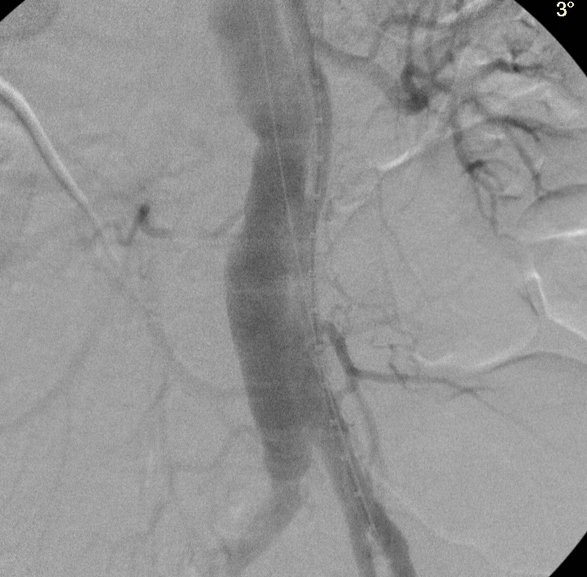

▲ 图5 近肾平面瘘口扩张满意

手术如期进行,经左上肢肱动脉穿刺,导丝途径左锁骨下动脉、胸主动脉夹层近端破口、假腔,在肾动脉平面附近成功经真假腔破口超选至腹主动脉真腔远端。并应用球囊、导管等扩大破口面积。这一步可谓之“神来之笔”,失败则手术无法进行,成功则双肾功能均得以保全。最后植入胸主动脉覆膜支架及限制性支架各1枚,复查造影提示近端瘘口封堵良好,真腔管径改善,双肾动脉灌注良好。术后复查CTA及肾功能提示双肾形态及血供良好,肾功能正常。